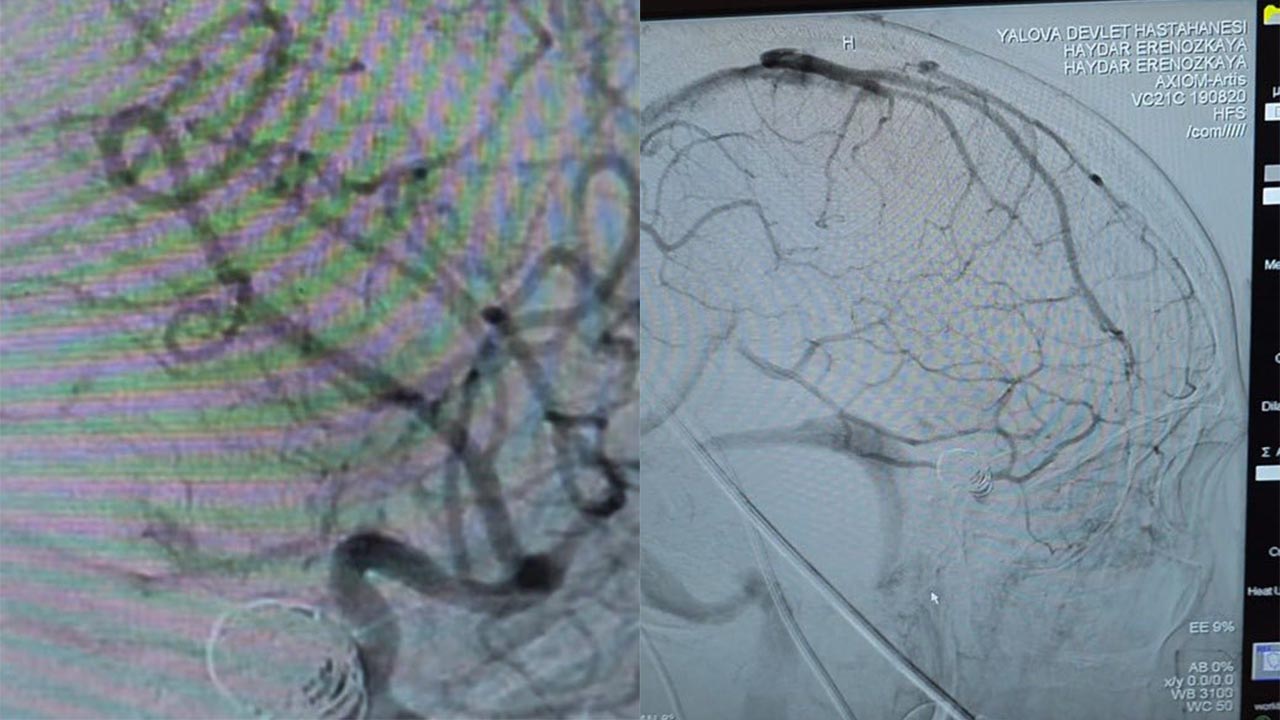

Acil servise bilinci kapalı olarak getirilen hasta, yapılan tetkiklerin ardından acil olarak endovasküler anjiyografi işlemine alındı. Kasıktan girilerek gerçekleştirilen coil ve stent uygulamasıyla anevrizma başarıyla kapatıldı. Operasyonun ardından hasta bilinci açık şekilde uyandı ve kısa sürede yürüyerek taburcu edildi.

Yalova Üniversitesi Tıp Fakültesi, yalnızca sınırlı sayıda merkezde uygulanabilen bu tür ileri düzey beyin cerrahisi girişimlerini artık kendi bünyesinde gerçekleştirebiliyor. Operasyonu gerçekleştiren Dr. Öğr. Üyesi Haydar Eren Özkaya ve ekibi, başarılarıyla sağlık camiasında dikkat çekti.